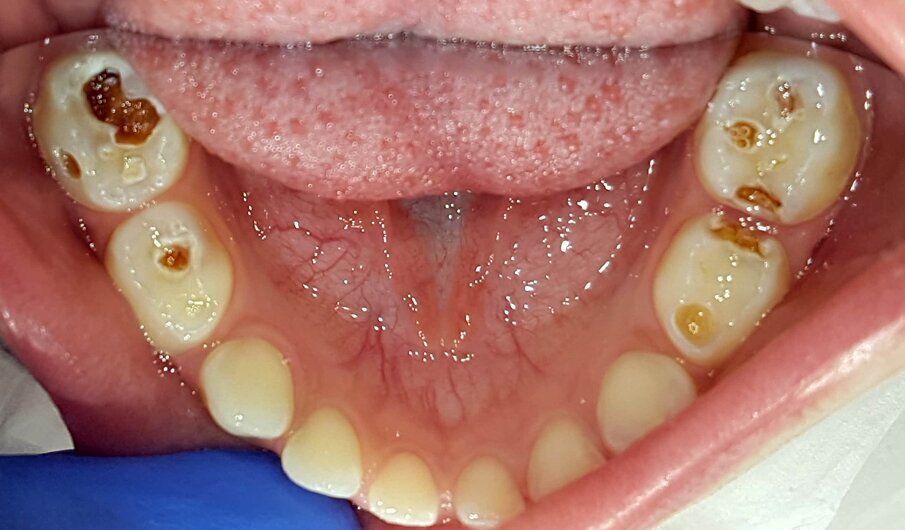

Een kind van vierenhalf jaar met multi-cariës werd verwezen voor behandeling onder narcose (afb. 6a-e). Klacht: lichte gevoeligheid .

Bij deze eerste sessie trainde ik het poetsen, opende ik de laesies voorzichtig en behandelde de laesies met SDF. Bij het monitoren zal blijken of er aanvullende behandelingen nodig zijn zoals herhalen SDF, SMART, Hall-kroon of lokaal een conventionele behandeling.

Afbeelding 6a. Multi-cariës bij intake.

Afbeelding 6b. Multi-cariës bij intake.

Afbeelding 6c. Multi-cariës bij intake.

Afbeelding 6d. Cariëslaesies vrijgelegd en SDF aangebracht. Evaluaties van de zelfzorg bepalen de balans tussen causale therapie en symptoombestrijding.

Afbeelding 6e. Cariëslaesies vrijgelegd en SDF aangebracht. Evaluaties van de zelfzorg bepalen de balans tussen causale therapie en symptoombestrijding.